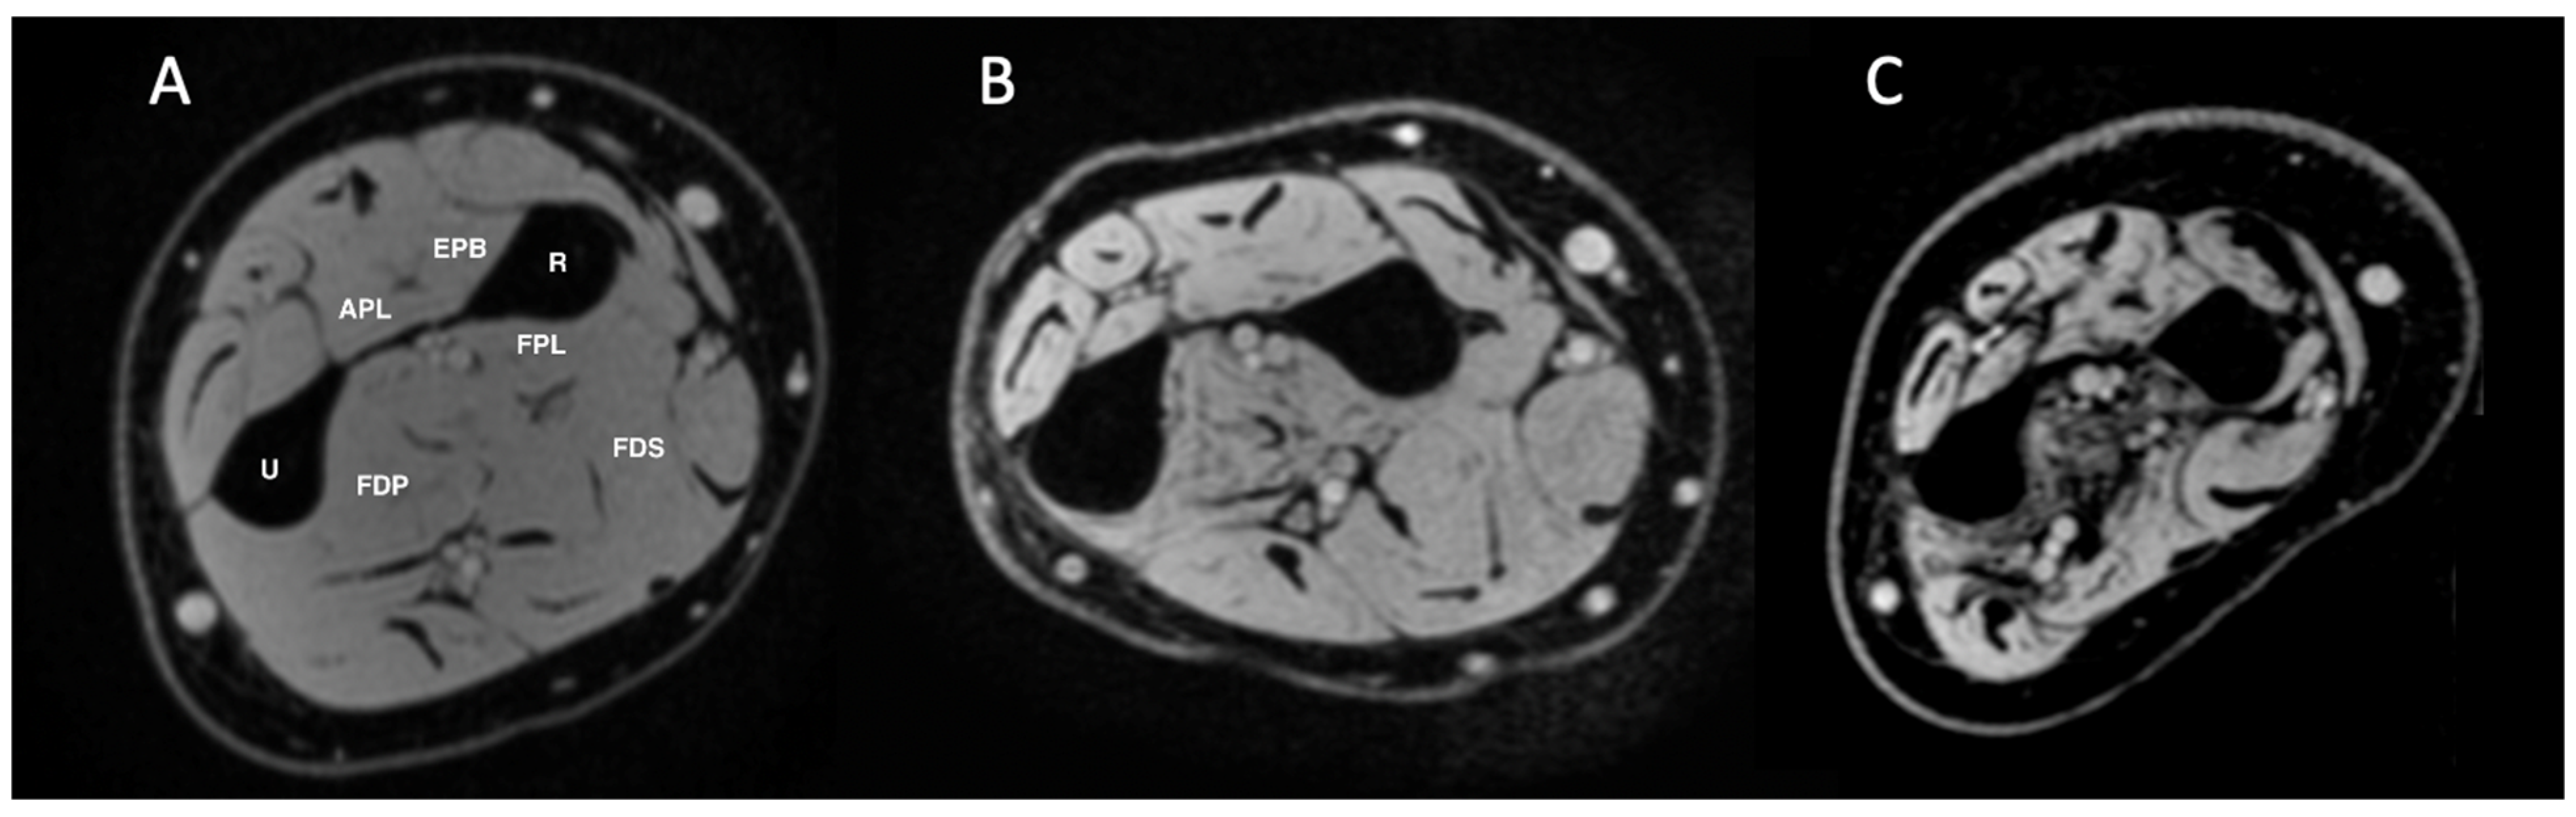

2.3. MRI Image Analysis

| FDP | Flexor Digitorum Profundus |

| FDS | Flexor Digitorum Superficialis |

| FPL | Flexor Pollicis Longus |

| EPB | Extensor Pollicis Brevis |

| APL | Abductor Pollicis Longus |